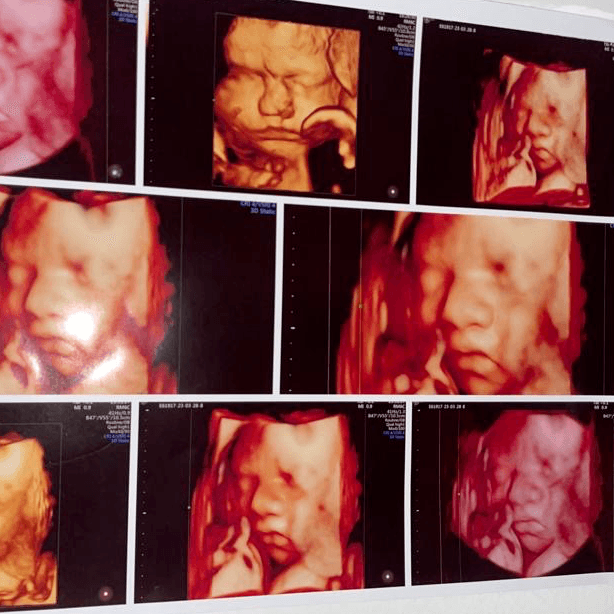

La ecografía 5D es una técnica avanzada que permite obtener imágenes tridimensionales en tiempo real del feto, ofreciendo una visualización más realista y detallada que las ecografías 3D y 4D.

20 min

$55.000 CLP